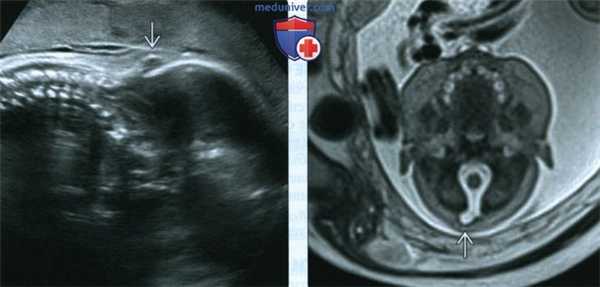

(Слева) УЗИ шейного отдела позвоночника в сагиттальной плоскости. Обнаружено затылочноеэнцефалоцеле небольших размеров Нарушение не было задокументировано во время данного исследования - энцефалоцеле было позднее обнаружено на МРТ плода, что заставило вернуться к ранее выполненным УЗИ и ретроспективно подтвердить находку.

(Справа) Тот же случай. МРТ основания черепа плода, Т2-ВИ, поперечный срез. Отчетливо визуализируется затылочное энцефалоцеле. Данная находка характерна для СЖ, однако часто упускается из внимания во время УЗИ, особенно если нарушение впервые появилось в III триместре.